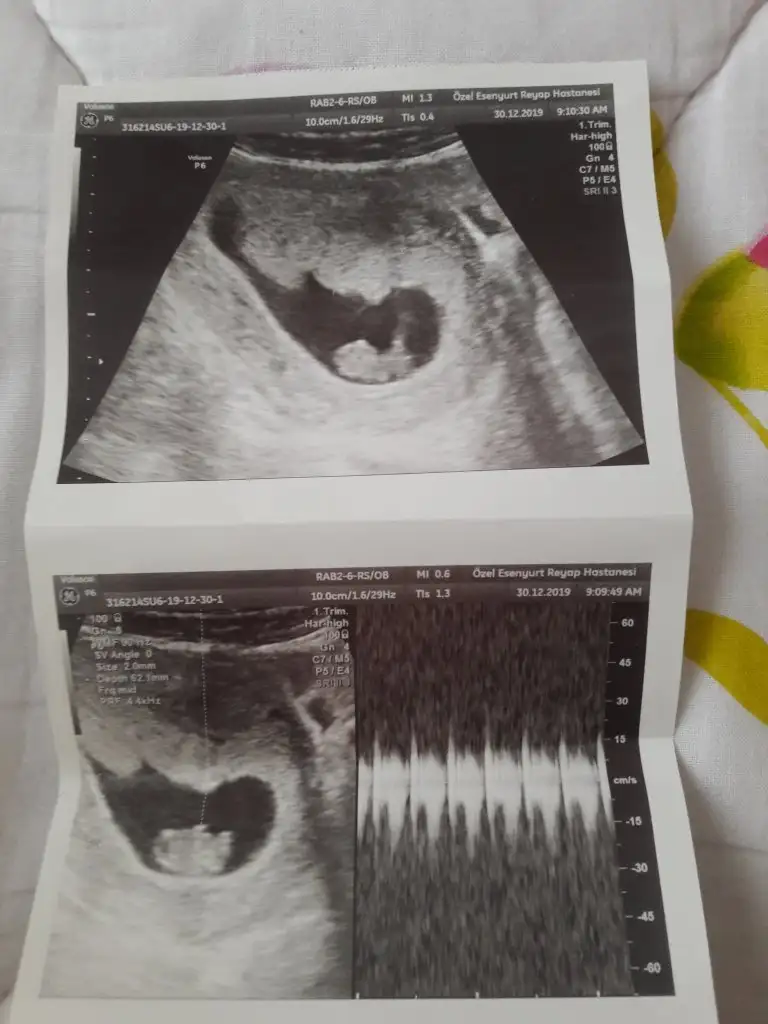

MaşAllah canımEki Görüntüle 2570165 bugün kontrolum vardı kizlar

Eki Görüntüle 2570165 bugün kontrolum vardı kizlar

Benim rahim ters vajinal baktı ve bebegide gördük ben 5+3um bugun